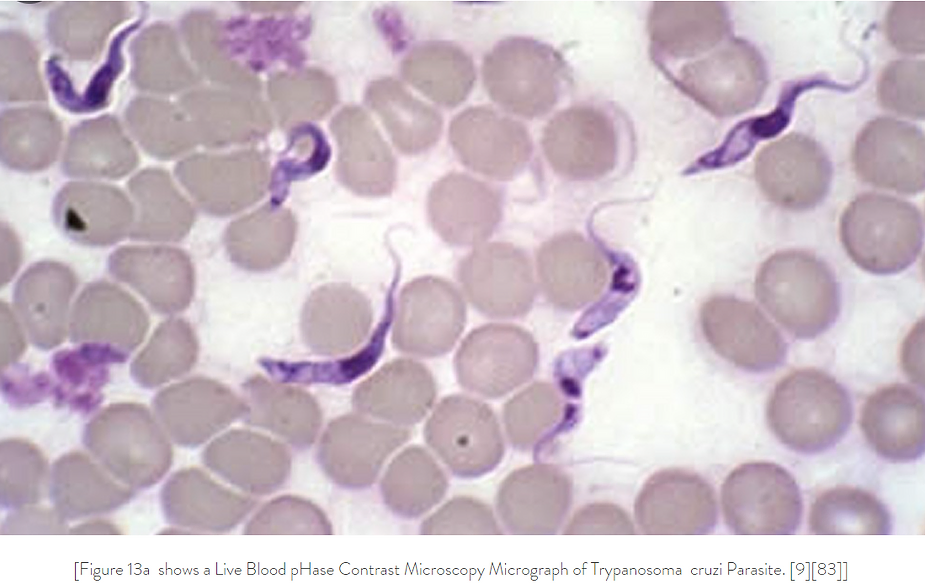

If you have been inoculated with the Pfizer VAXXXINE you may have been injected with a biochip of reduced graphene attached with ferric oxide and the eggs of the Trypanosoma Cruzi parasite! Check out the micrographs below!

Graphene Ferric oxide crystals (Ferromagnetic Properties) and Trypansoma cruzi parasite eggs were observed in the live capillary blood from a VAXXinated male using Brightfield, pHase contrast microscopy and confirmed with UV absorbance and Fluorescence Spectroscopy, Scanning Electron Microscopy, Transmission Electron Microscopy, Energy Dispersive Spectroscopy, X-ray Diffractometer and Nuclear Magnetic Resonance instruments. – Copyright Hikari Omni Media – Robert O. Young MSc, DSc, PhD, Naturopathic Practitioner – 2021

Using GO to deliver any vaXXXine is diabolical, then add mRNA and Trypanosoma cruzi parasites and you have a truly evil group of murderers.